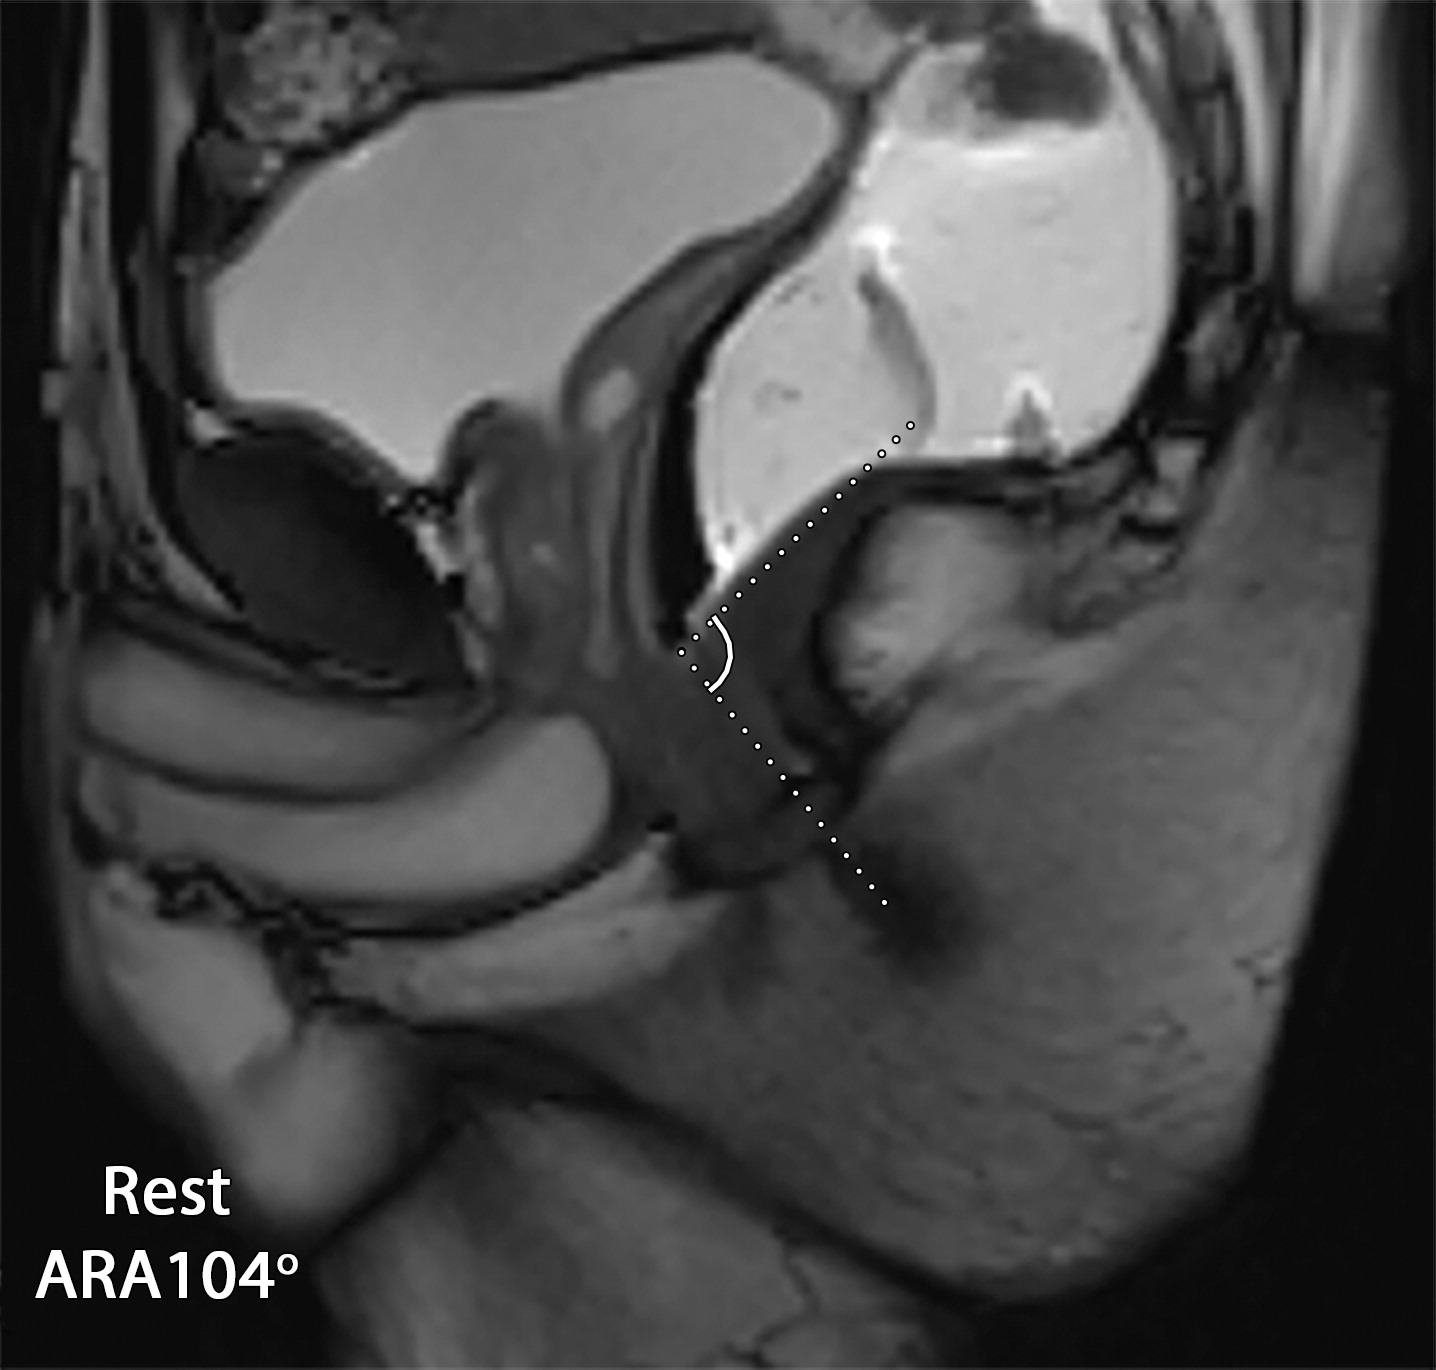

a54a1cb8cfeaf259eec8f4d8f79de20f.jpeg5bd0d167d41482a652f0e12d75b5e4a4.jpeg9414a04737a9077a8760c398f38476f8.jpeg

肛门直肠角(ARA);

28岁协同动作障碍患者,a图静息态ARA为104°,b图在排便时ARA为86°,这是由于耻骨直肠肌的反常收缩。c图示双侧耻骨直肠肌增厚(c图白色长箭头)。